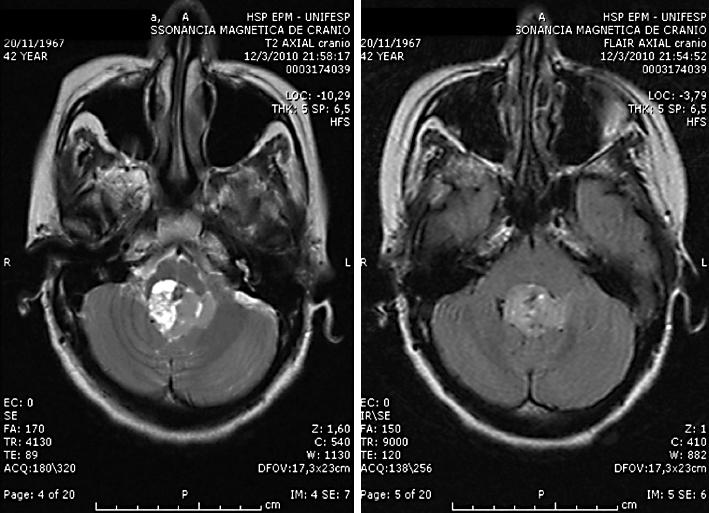

中枢性神经源性呼吸衰竭:一项具有挑战性的诊断。

Central neurogenic respiratory failure: a challenging diagnosis.

Central nervous system lesions are rare causes of respiratory failure. Simple observation of the breathing pattern can help localize the lesion, but the examiner needs to be aware of potential pitfalls such as metabolic or pulmonary alterations.

We describe 3 cases in which central neurogenic respiratory failure occurred simultaneously with other alterations or in an unusual presentation.

All patients were diagnosed with central neurogenic respiratory failure and treated for it with good recovery.

Central neurogenic respiratory failure is a challenging diagnosis and needs to be reminded in difficult-to-wean patients carrying inconclusive evidences of metabolic or pulmonary alterations.